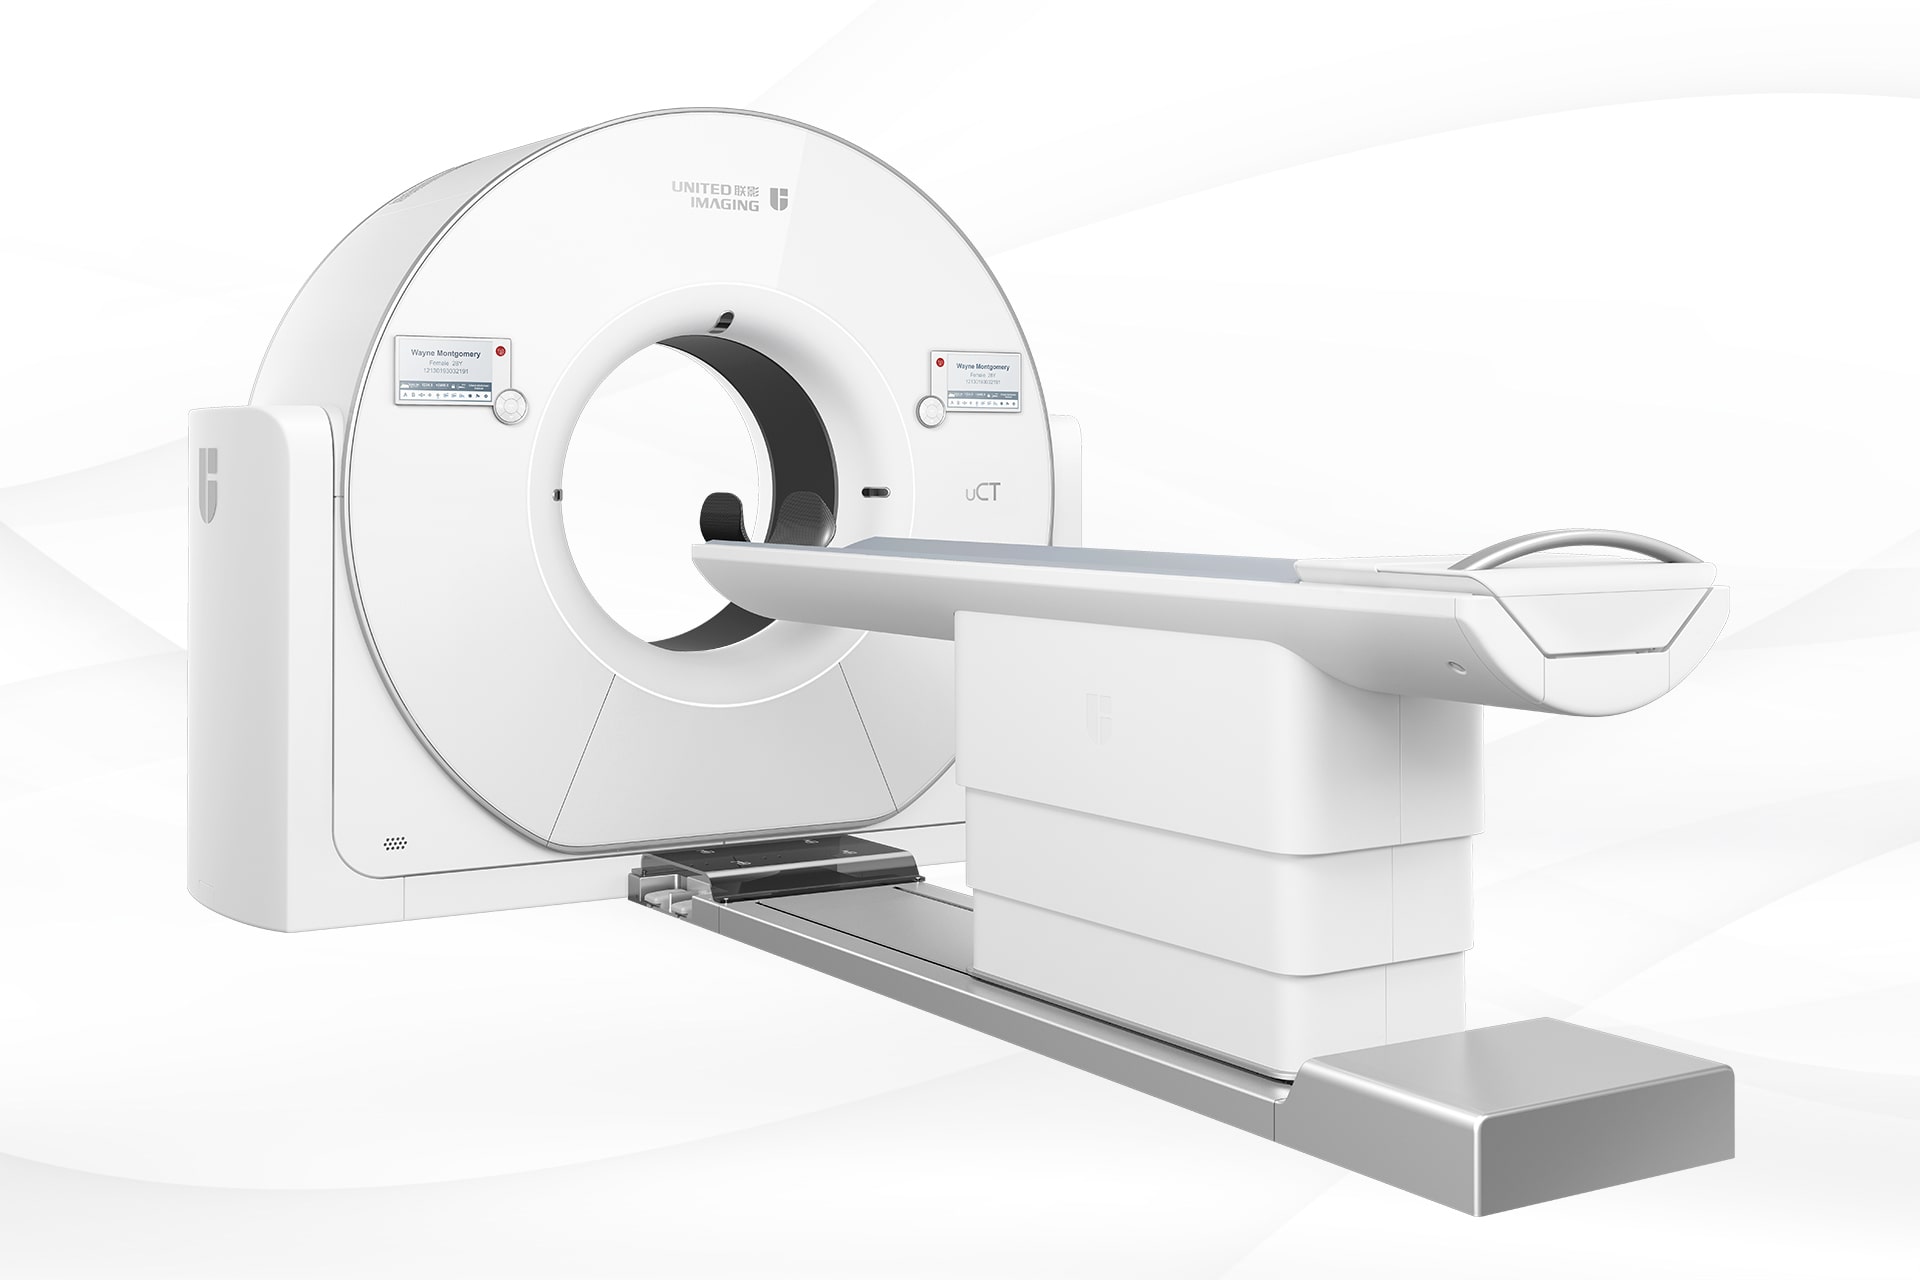

中国首款超高端640层CT

中国首款超高端640层CT

近日,科技部重点研发计划数字诊疗装备研发重点专项成果汇报会暨2021国产超高端CT创新论坛在沪召开。政产学研医领袖精英聚首论道,品鉴分享「中国首款超高端640层CT——天河640」临床科研多病种、全场景应用。天河640的自主研发,带动了本土产业链整体升级,标志着我国在CT领域实现了临床科研大设施自主可控,将进一步推进重大疾病攻关能力自主可控,助力国家医学高峰高地建设。

我国是心脑血管疾病高发国家,心血管病死亡率居各类疾病之首;脑卒中发病风险位居全球首位。超高端CT是此类疾病诊断利器,但因技术壁垒高筑,数十年未实现国产化。进口设备运营成本高,更难以针对国内临床实际需求快速响应与定制化开发。依托「十三五」国家重点研发计划「数字诊疗装备研发」重点专项,聚合产学研医跨界力量,联影医疗成功研制中国首款超高端640层CT,并在人工智能应用、智能重建算法等领域取得一系列创新成果。

天河640具备完全自主知识产权,搭载业内最宽16厘米探测器、业内最快的0.25秒/圈机架转速、业内最多的320排探测器排数、以及业内最大的82厘米机架孔径,天河640代表了当前CT设备制造领域最先进的技术水平,结合前沿AI人工智能技术,可为创新临床应用和科研探索解锁无限想象空间。